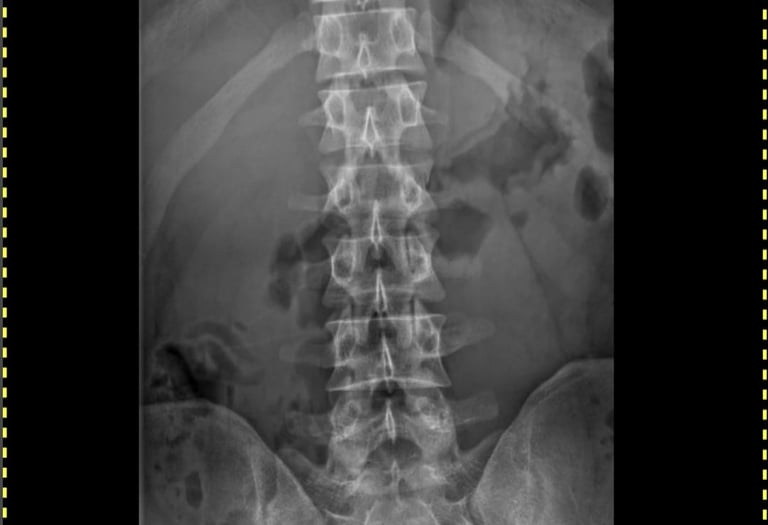

Spinal X-rays

Specialized digital X-rays for the Cervical, Thoracic, and Lumbar spine regions. We provide precise imaging for back pain, posture evaluation, and Road Accident Fund (RAF) radiological reports.